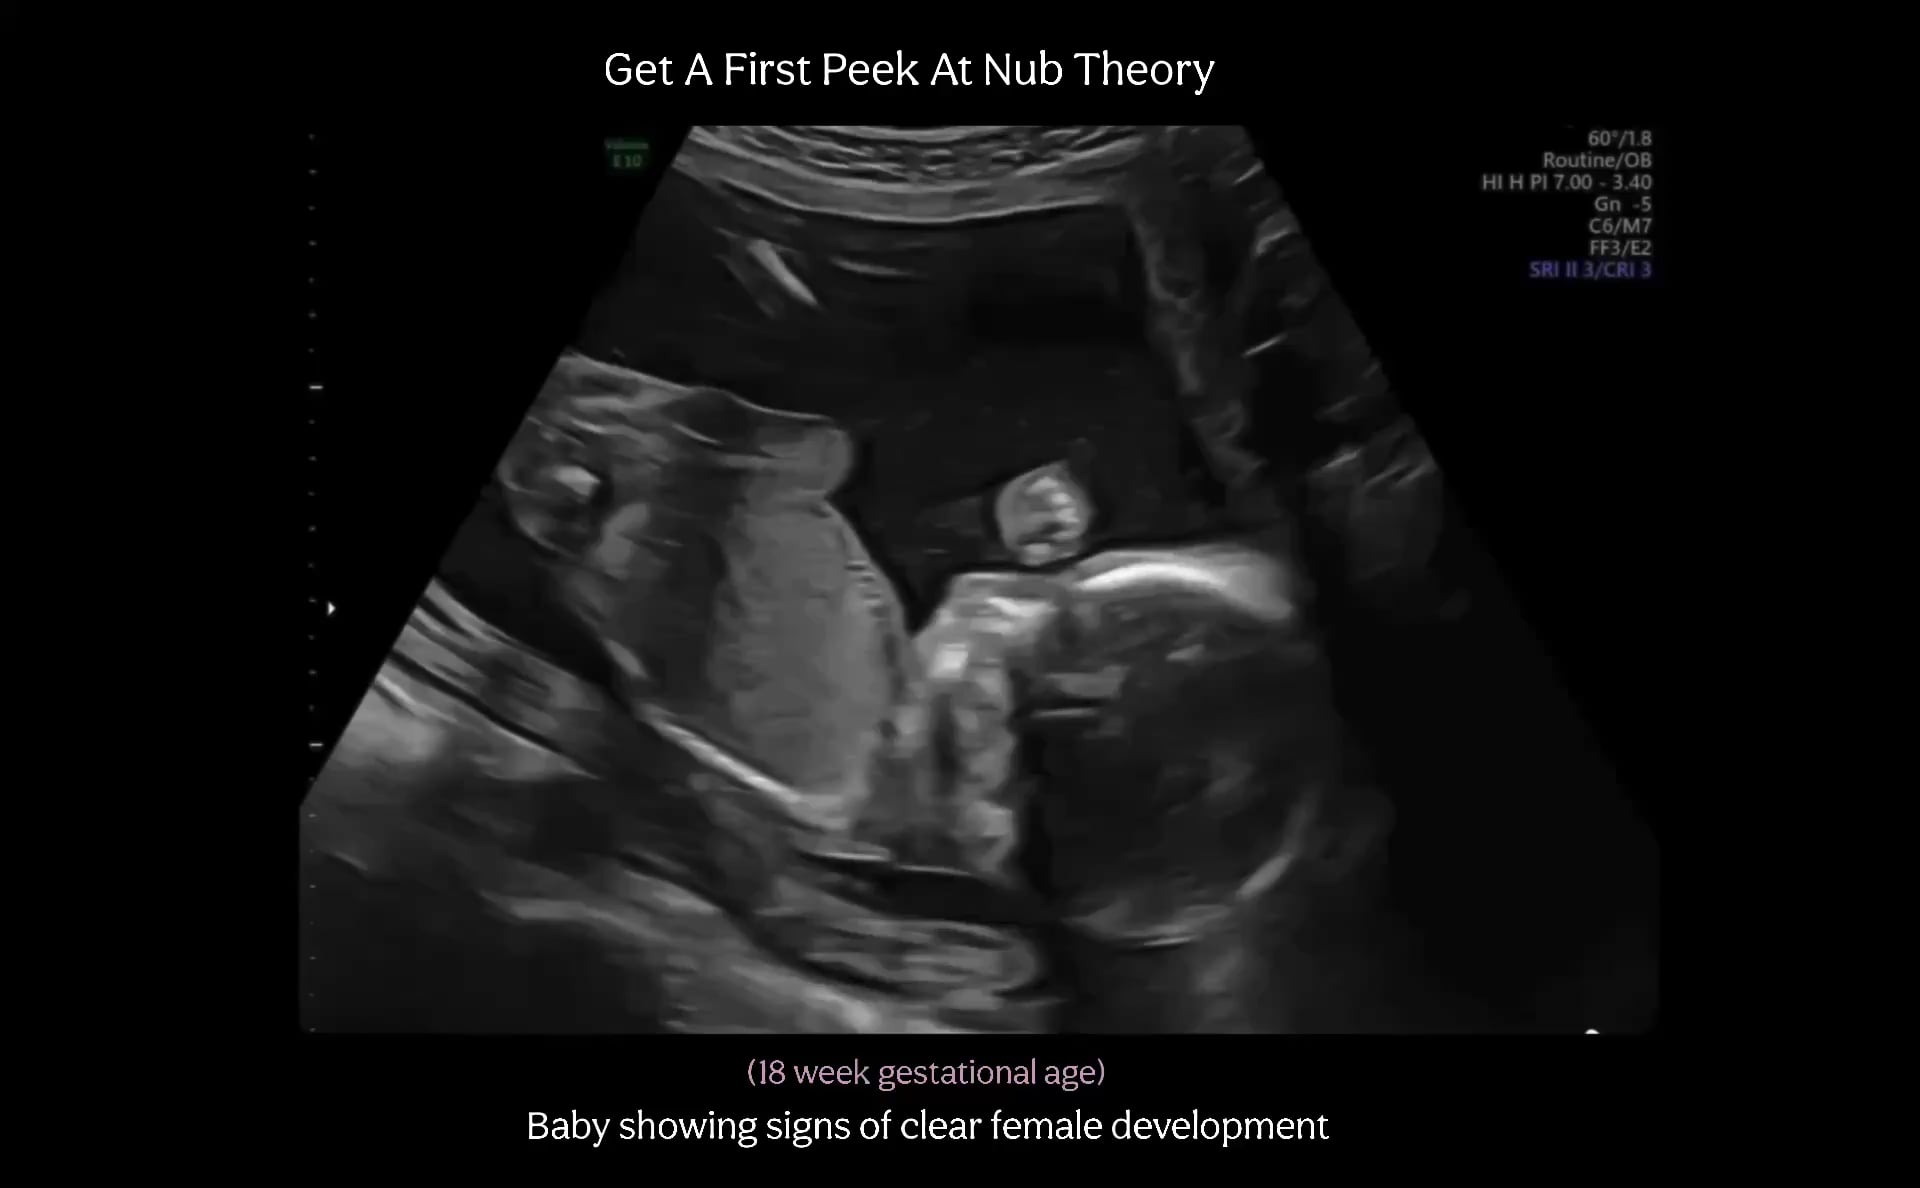

At First Peek Gender Prediction we aim to provide you early gender prediction results that you can trust.

Our team are two wonderful moms who were just like you anxiously waiting to discover the gender of our own babies. At one point in our parenting journey, we discovered the Nub and Ramzi Theory Methods and absolutely loved looking at ultrasounds. After predicting correctly for years on hundreds of scans and researching and studying them. We decided to start our own business. Giving you a company that you can trust. We are known for our honesty when it comes to your baby’s gender.